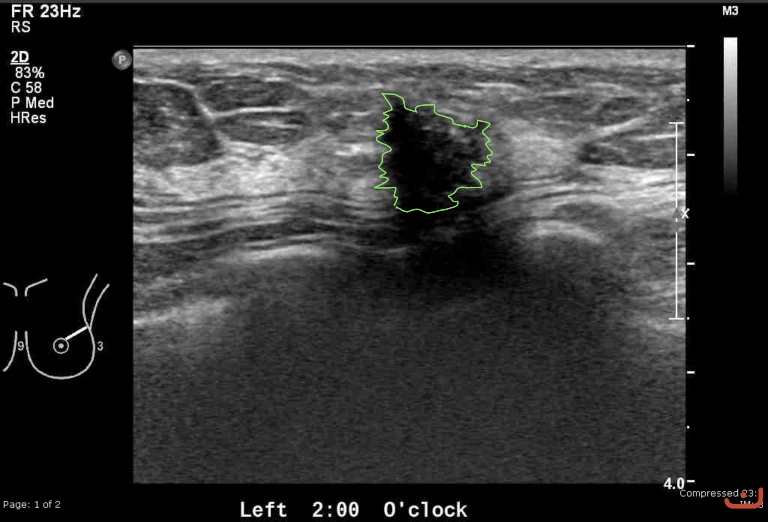

Case 19-G1

Malignant solid mass

Friday, 22 May 2015

183.80 KB (768 x 522 px)